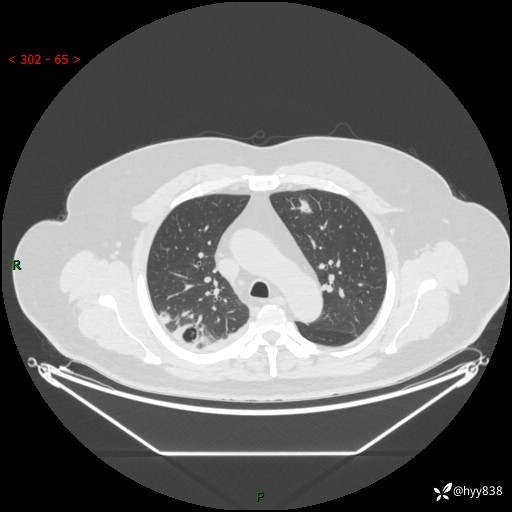

病例信息

性别:男

年龄:48岁

简要病史:发热来诊(门诊病人)

胸部CT平扫